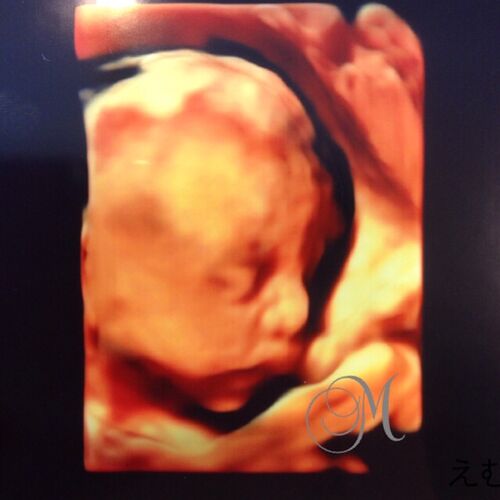

4Dエコー画像が嬉しい!妊娠7か月(24週)の妊婦検診。

妊娠7か月(妊娠24週)の4Dエコー画像。 今日から、妊娠7か月です。そして、妊婦検診に行ってきました。お腹の赤ちゃんは順調に育ってました!私が通っている杉山産婦人科には、4Dエコーの設備があります。が、毎回撮影してもらえるわけではありません。 先…